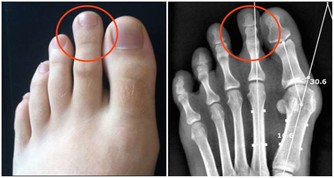

4、晚餐與尿結石人的排鈣尖峰期在餐后的4 、5小時,若晚餐太晚吃,當排鈣尖峰期到來時,通常已進入睡眠中,於是尿液滯留在輸尿管,膀胱尿道等尿路中,不能及時排出體外,致使尿中鈣不斷增加,容易沉積下來形成小晶體,長期下來就擴大形成結石。男人做菜顯魅力,女人做菜顯賢惠。